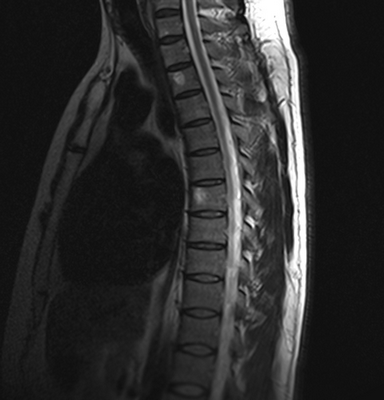

Снимок МРТ поясничного отдела позвоночника в сагиттальной проекции при остеохондрозе

МРТ поясничной области - современный метод диагностики патологических процессов, ограничивающих функциональность нижних отделов позвоночника. Магнитно-резонансная томография проходит без хирургических манипуляций, процедура безболезненна и безопасна для пациента. Метод визуализирует расположение костных элементов, хрящей, состояние мягких тканей, невральных структур и кровеносных сосудов.

В основе исследования лежит использование магнитного поля, которое влияет на размещение диполей воды в клетках организма. Молекулы Н2О меняют свое положение, интенсивность сигнала напрямую зависит от насыщенности тканей жидкостью. Специальные датчики считывают информацию, сложная компьютерная программа обрабатывает данные, преобразуя их в серию послойных изображений изучаемой зоны.

Наиболее информативно МРТ в отношении рыхлых структур: нервных и мышечных волокон, клетчатки, связочного аппарата и сосудистой системы поясничного отдела позвоночника. В результате сканирования врач получает фотографии исследуемой области, сделанные в трех проекциях на заданной глубине. Толщина шага при МРТ составляет от 1 мм.